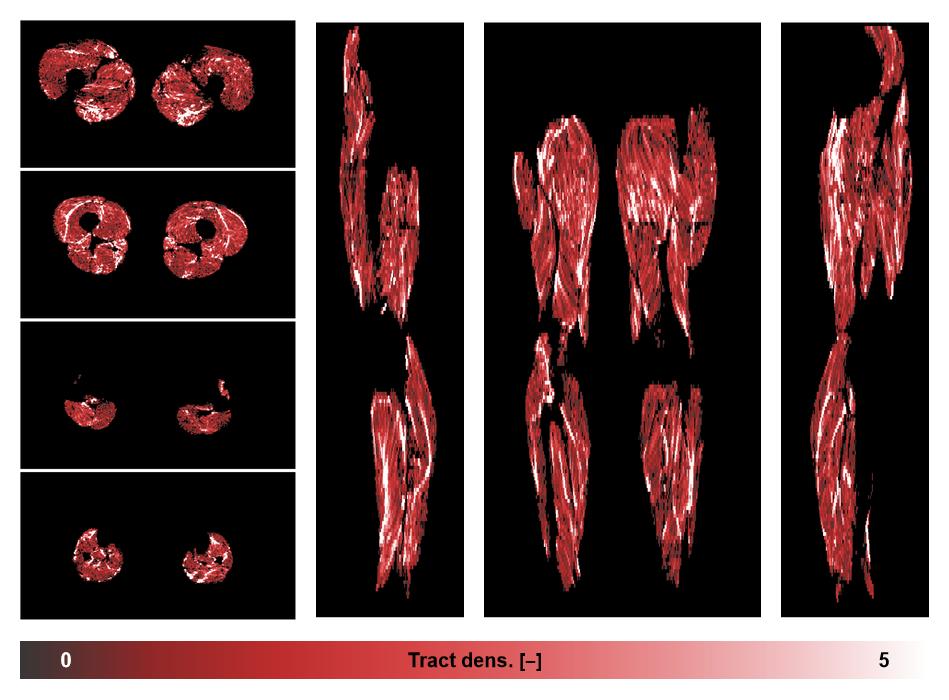

• Muscle fiber density map

Muscle fiber tract density map based on whole leg DTI based fiber tractography.